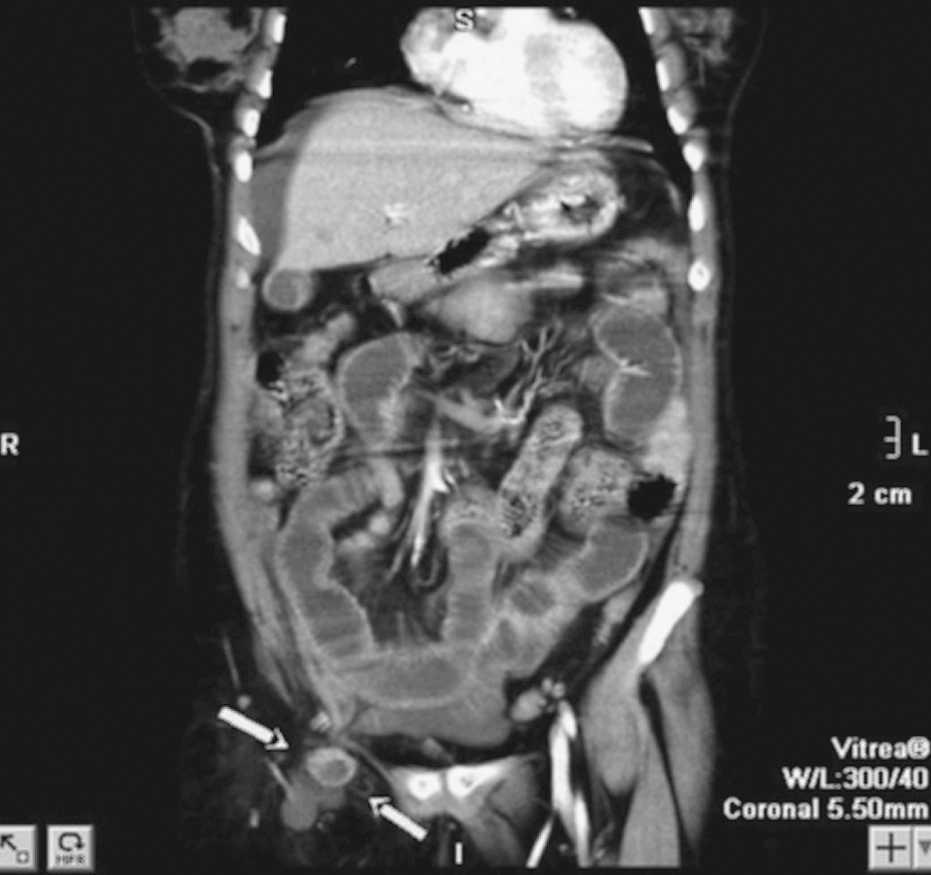

Mujer de 50 años sin antecedentes de interés ni intervenciones quirúrgicas. Acude al servicio de urgencias con cuadro de dolor abdominal brusco de pocas horas de evolución, centro abdominal tipo cólico, que se acompaña de vómito y episodio de hipotensión, así como fiebre de más de 38 °C. Previamente no había tenido dolores similares. En la exploración se objetiva abdomen blando con molestias a la palpación profunda en FID, sin defensa ni peritonismo. La bioquímica general y el hemograma no muestran alteraciones, a excepción de una marcada leucocitosis con desviación izquierda. La radiografía simple de abdomen presenta un asa centroabdominal dilatada sin patrón obstructivo. Las imágenes obtenidas con tomografía computarizada multicorte (reconstrucción multiplanar, plano coronal) muestran una hernia crural derecha que contiene un asa de íleon distal con signos de sufrimiento intestinal y condiciona obstrucción retrógrada de intestino delgado, con moderada dilatación de las asas y niveles hidroaéreos en su interior. Moderada cantidad de líquido libre. Con el diagnóstico de hernia crural incarcerada se realiza una hernioplastia crural derecha por vía preperitoneal y se objetiva un atrapamiento de asa en borde antimesentérico, que se recupera sin incidencias tras reducción de la hernia, sin precisar de resección intestinal.

Fig. 1.

Diagnóstico: Obstrucción intestinal secundaria a hernia crural incarcerada.